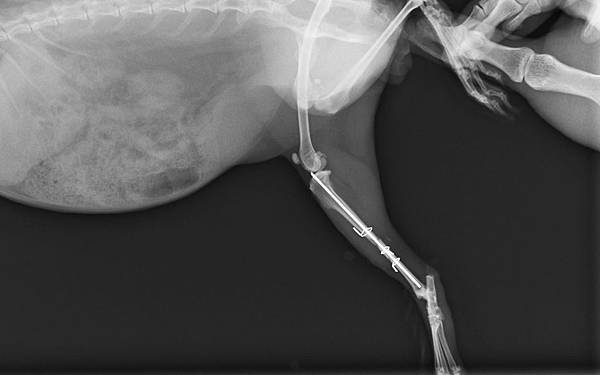

70_205_20120329235008.0 手術後側照

70_206_20120329235205.0  手術後正照

手術採取骨髓內釘合併環紮鋼線修復,手術後配合軟包紮及限制活動4周,癒合良好